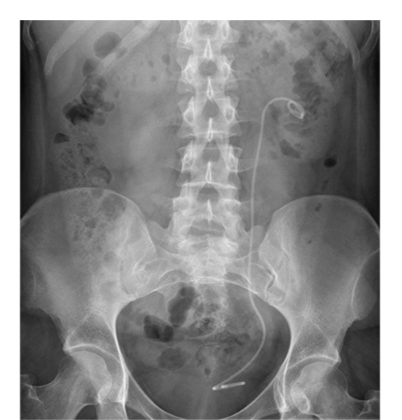

**What is the artifact shown in this image?** Naso-jejunal tube Colonic stent Pig-tail (JJ) stent Percutaneous nephrostomy tube Inferior vena cava (IVC) filter

**Pig-tail (JJ) stent** A ureteric stent has been placed to relieve ureteric obstruction The catheter has loops (pig-tails) at both ends which hold it in place